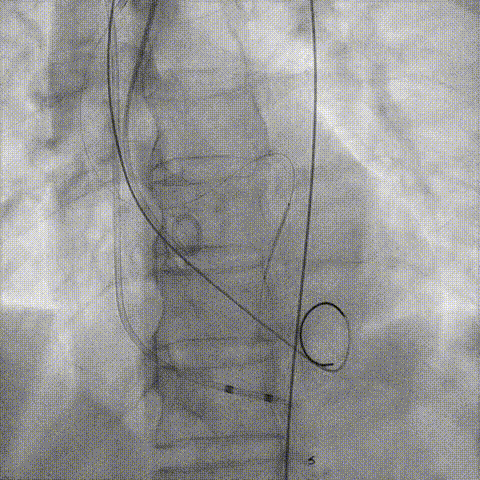

Telescope™+Runthrough

18mm*40mm 预扩张

预埋 Resolute Integrity 3.5*26mm

再次评估左冠开口

预置Telescope™导引延长导管及导丝保护左冠,

18mm球囊预扩张再次评估冠脉闭塞风险。